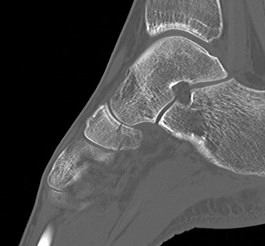

Imaging

Acute, minimally displaced navicular fracture

Acute displaced navicular fracture